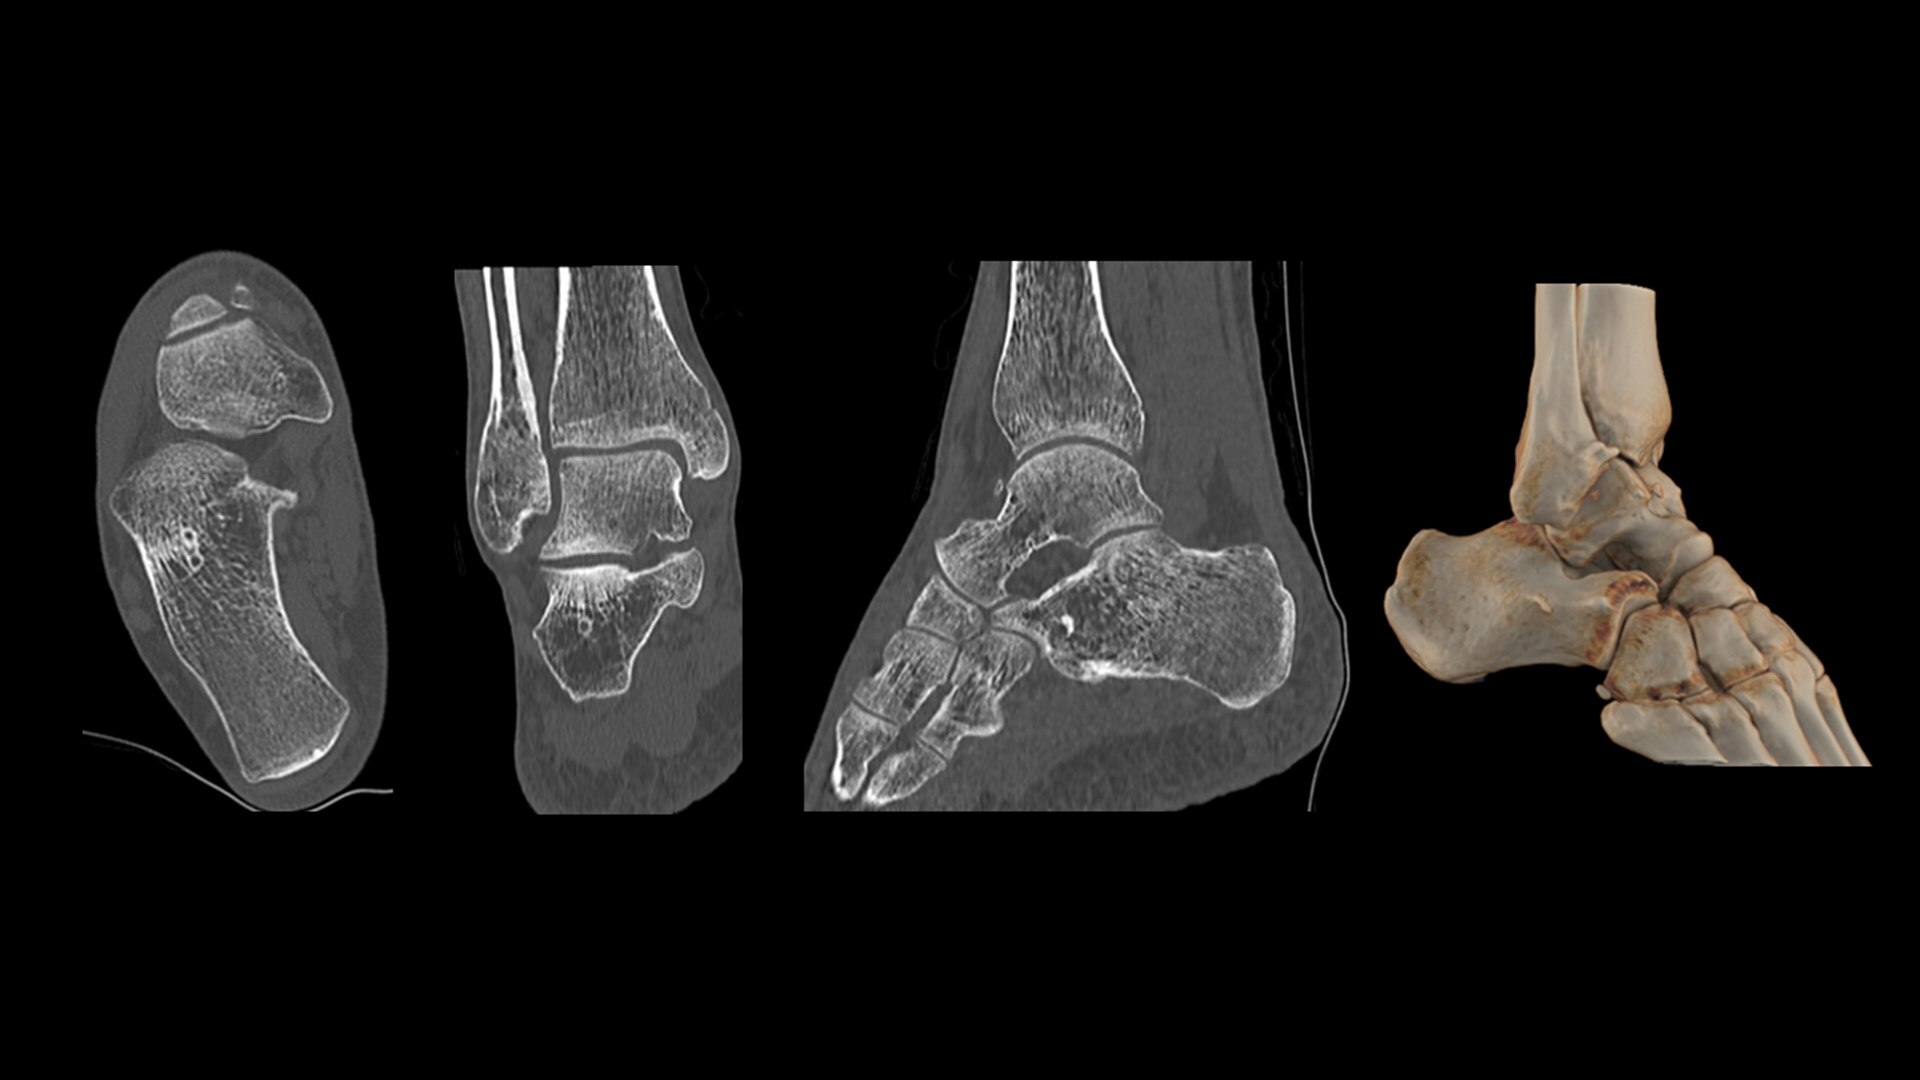

Cardiac CT has become a front-line, non-invasive imaging tool for diagnosing, treatment planning and monitoring of cardiovascular disease

Healthcare providers are striving to improve patient health but are struggling with increasingly complex exams, insufficient or inexperienced staff, and operational and capital efficiency. Revolution™ Vibe, designed to deliver leading-edge technology, features advanced cardiovascular capability. It improves patient access and operational efficiency, prioritizes patient care and supports your facility's growth with lower lifecycle costs.

Unlimited 1-Beat Cardiac is designed to provide consistent, high-quality imaging for accurate diagnoses, even in challenging patients with atrial fibrillation, breath-holding difficulties, heavily calcified coronaries, in-stent restenosis, and situations where an ECG trace is unavailable.